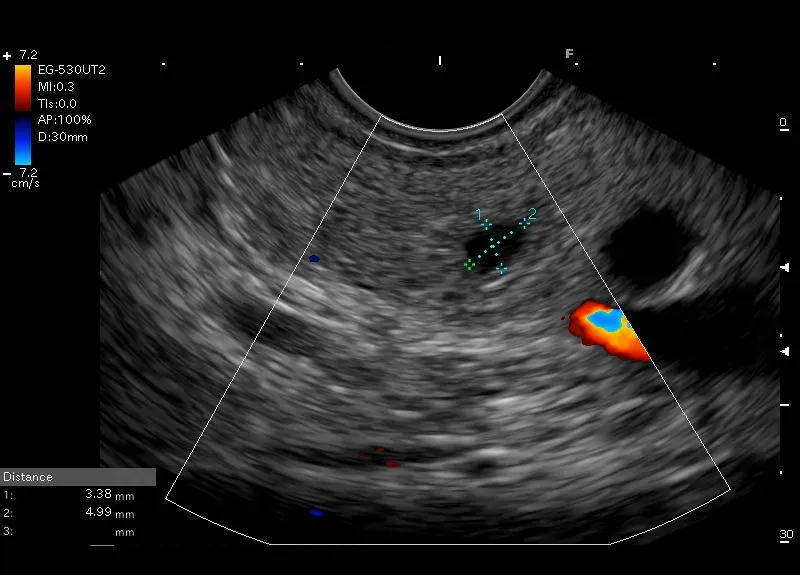

Położona w trzonie trzustki drobna, około 4 / 5 mm  bezechowa przestrzeń o wyraźnych granicach, bez struktur wewnętrznych i bez przepływu naczyniowego widocznego w opcji Doppler-drobna torbiel trzustki